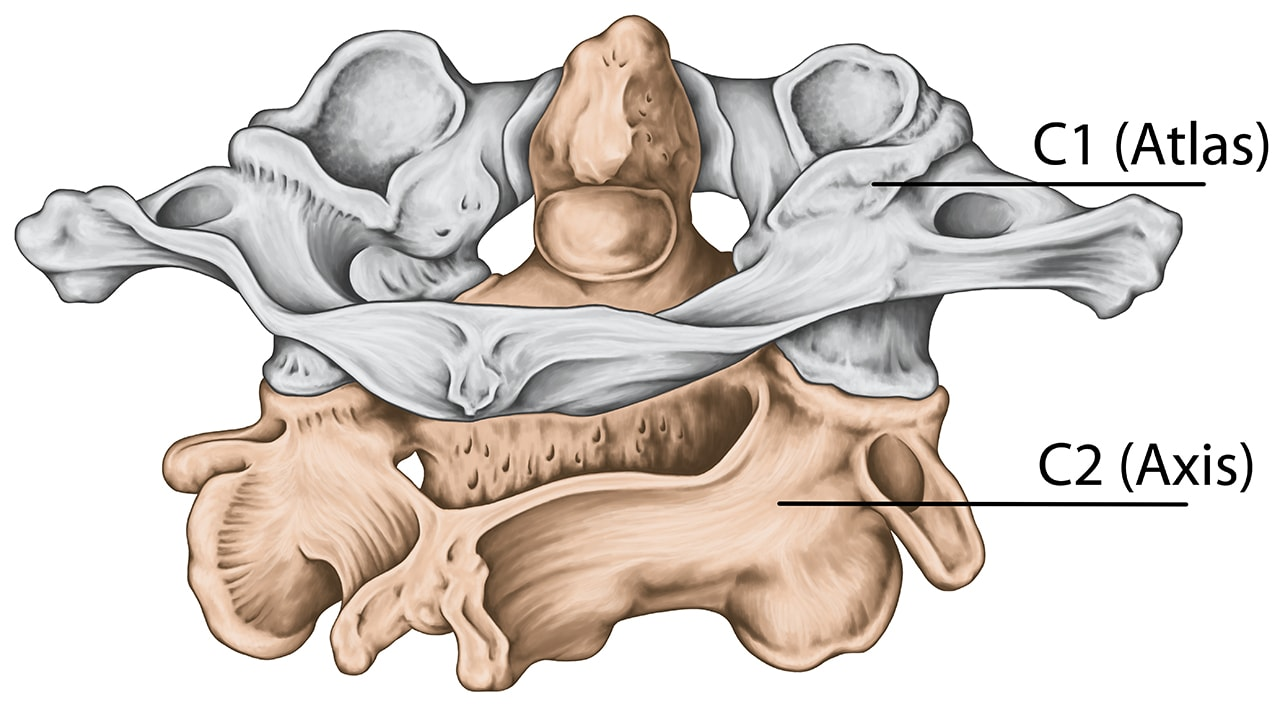

What is the major distinguishing feature of C1 (atlas)?

It lacks a vertebral body, which fuses onto the body of C2 during development to form the dens of C2.

What is the structural composition of the atlas (C1)?

the atlas is ring-shaped and composed of two lateral masses interconnected by anterior and posterior arches